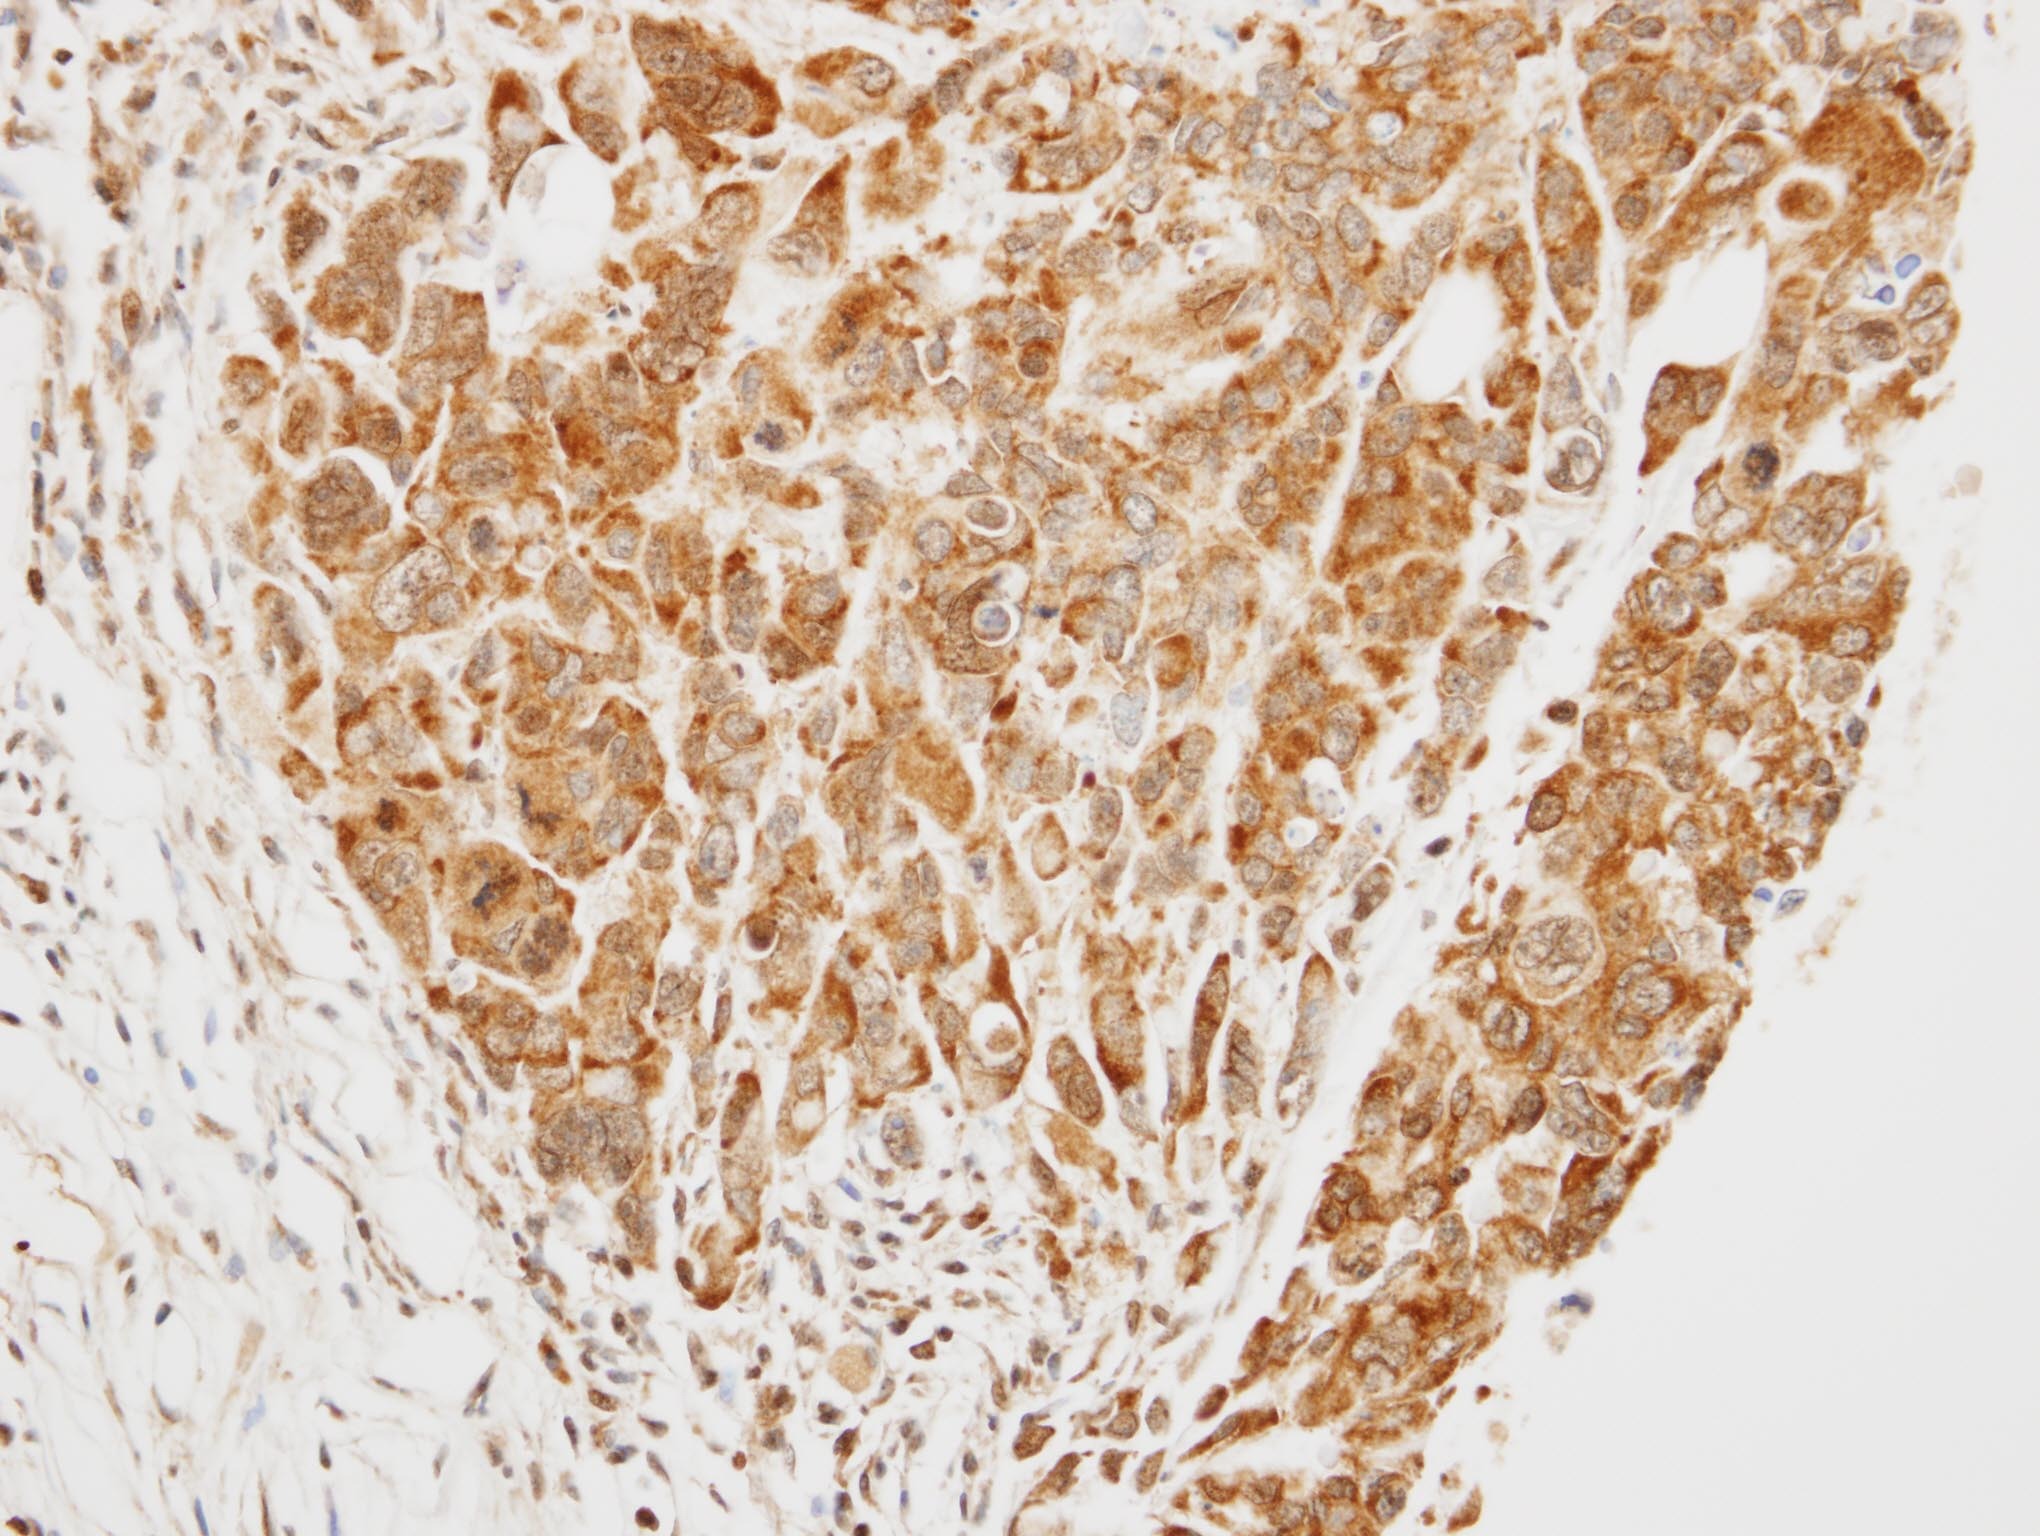

Supportive validation

- Submitted by

- Signalway Antibody LLC (provider)

- Main image

- Experimental details

- Immunohistochemical analysis of paraffin-embedded SW480 xenograft, using TRIM37 antibody at 1: 1000 dilution.